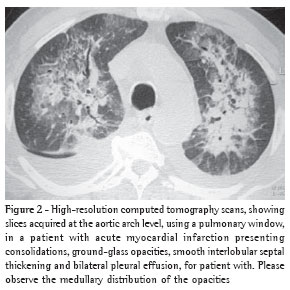

Overall, ground-glass opacities and thickening of the interlobular septa were the most common findings, occurring in 100% of the cases (Figures 1 and 2).

The thickening of the interlobular septa was bilateral in thirteen cases (Figures 1-4) and unilateral in two, also in the patients with fibrosing mediastinitis. In all cases, the thickening was of the smooth type.

All cases of interlobular septal thickening (100%) were accompanied by ground-glass opacities. Nevertheless, the mosaic pattern of attenuation was observed in only ten cases (66%) (Figure 1).

Pleural effusion was the third most common tomographic finding overall and was the most common nonparenchymal finding, being found in 13 patients (87%), predominantly in the bilateral form (n = 11) (Figures 1-3).